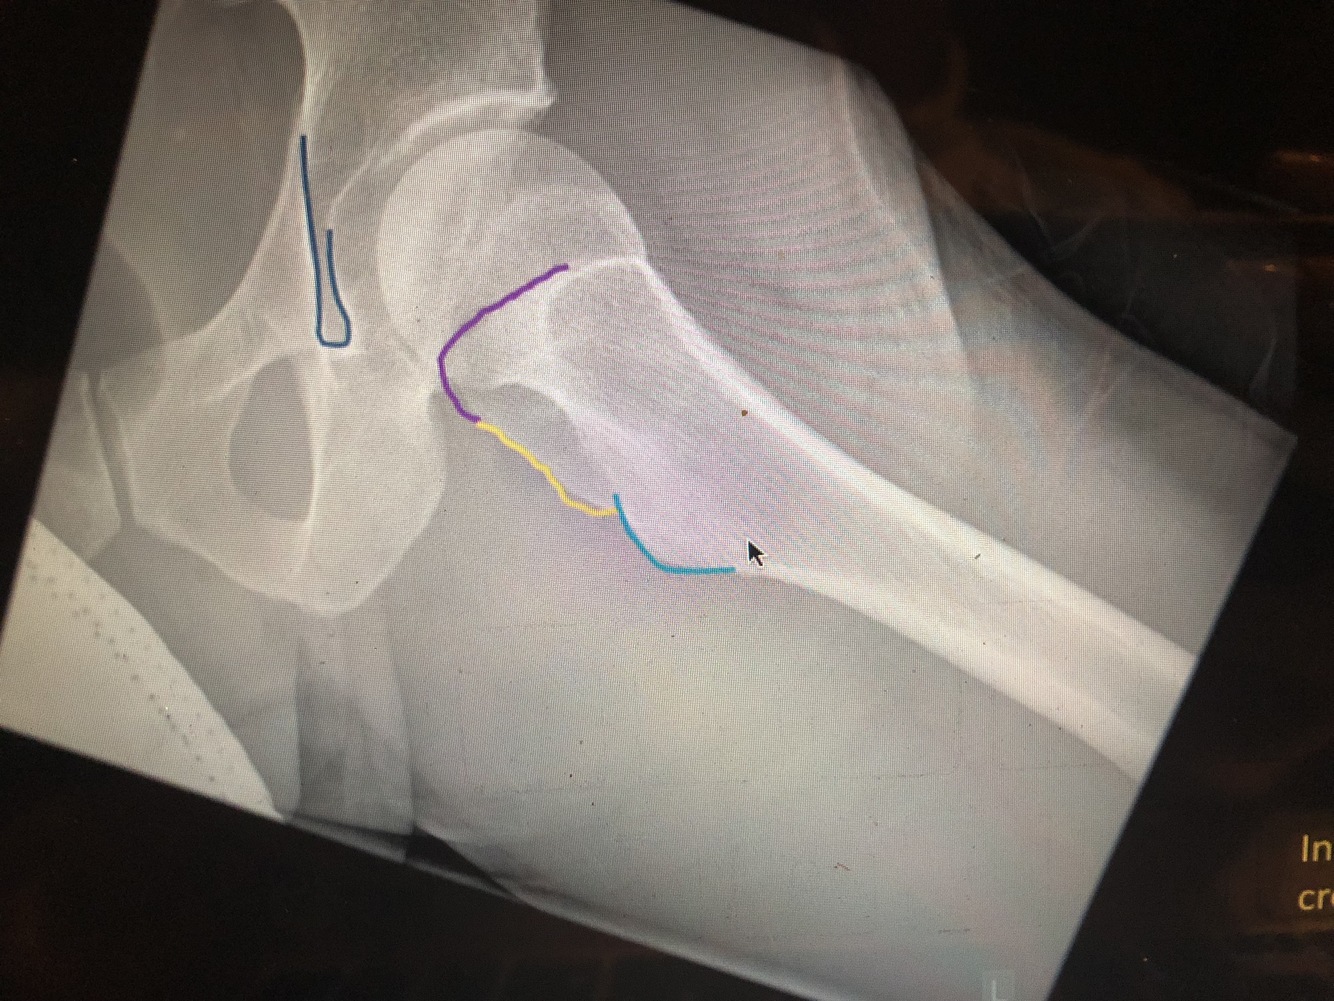

What is the dark blue line?

Kohler’s teardrop

What is the purple line?

greater trochanter

What view is this?

Frog leg

What is the light blue line?

lesser trochanter

What is the yellow line?

intertrochanteric crest